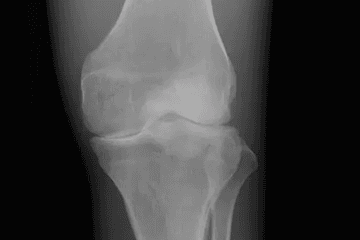

Hyaluronan is a naturally occurring polysaccharide found throughout the body, with particularly high concentrations in synovial fluid. In young, healthy joints, hyaluronan acts like a thick, gloopy lubricant that cushions cartilage, supplies nutrients to joint tissues, and shields cartilage from inflammatory compounds. When hyaluronan levels decline with age, the synovial fluid becomes thin and watery, losing its protective qualities. The result is that cartilage tissues begin to grind against each other, become starved of oxygen and nutrients, and lose their ability to regenerate.